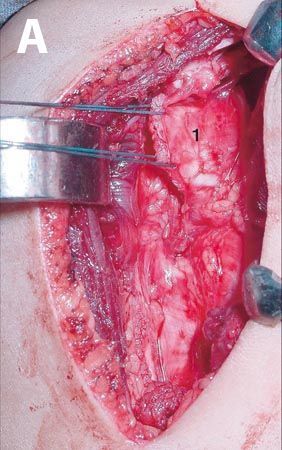

Intérêt de l’arthroscopie dans la prise en charge des fractures articulaires du radius distal